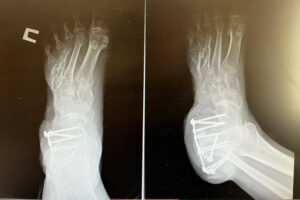

Как рассказали в медучреждении, к ним на лечение попал боец СВО. Он во время выполнения боевого задания наступил на мину. Взрыв буквально разорвал ступню на фрагменты. В ближайшем прифронтовом госпитале военные врачи совершили невозможное: остановили кровотечение, собрали оставшиеся куски стопы и сшили их, после чего эвакуировали раненого в тыл. Формально ногу удалось сохранить, однако её опорная функция оказалась под угрозой — взрывом был утрачен значительный участок плюсневой кости.

В течение пяти часов над пациентом одновременно работали травматологи и пластический хирург. Травматолог забрал фрагмент тазовой кости для её последующей пересадки в область стопы, потребовался трансплантат внушительных размеров: выпиленный фрагмент достигал 6,5 сантиметра в длину, 1,5 сантиметра в ширину и 1 сантиметра в толщину. Прежде чем имплантировать, хирурги подточили его точно по нужной форме.